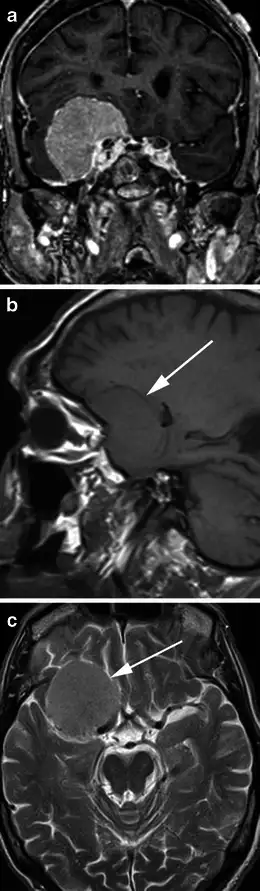

辐射对人体的伤害往往需要数年甚至数十年才能显现。在以色列的头癣受害者中,最早的癌症病例出现在1960年代末。1974年,以色列流行病学家巴鲁克·莫丹在《柳叶刀》杂志发表了一项开创性研究,追踪了约一万名在1950年代接受过头癣治疗的儿童。研究发现,与普通人群相比,这些儿童在成年后患头颈部肿瘤的风险显著增加——甲状腺癌的风险高出三倍,脑膜瘤的风险高出四倍,唾液腺癌的风险高出七倍。

莫丹的研究引发了医学界的广泛关注,也促使以色列政府开始正视这个问题。后续的研究进一步证实了辐射的长期危害。甲状腺是儿童辐射暴露后最易受影响的器官,因为甲状腺组织对辐射高度敏感,而儿童的甲状腺正处于快速发育阶段。接受过头癣治疗的儿童,其甲状腺癌发病率是普通人群的十八倍。更令人担忧的是,这些癌症往往在患者三十至五十岁时才被诊断,错过了最佳治疗时机。

脑膜瘤是另一种常见的辐射后遗症。这是一种起源于脑膜的良性肿瘤,生长缓慢但可能压迫大脑,导致头痛、癫痫和认知功能障碍。研究显示,儿童时期接受过头癣治疗的人,其脑膜瘤的发病率是普通人群的四倍以上。一些患者在几十年后才被发现脑中长有肿瘤,而此时肿瘤已经巨大,手术风险极高。